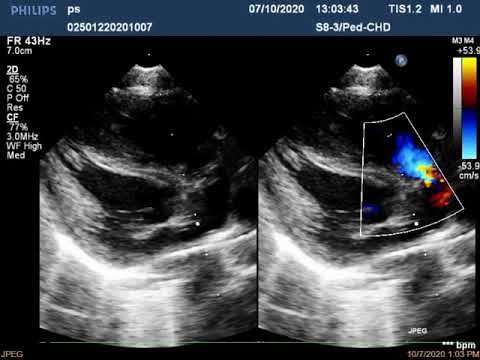

Эхокардиографическая оценка коронарных артерий при болезни Кавасаки. Климишин Ю.И.

Эхо КГ с анализом стеноза легочной артерии (рус. перевод)